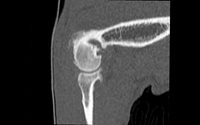

- Exploration des arthropathies de l'épaule : Ténosynovite, Ostéochondrite, Instabilités et lésion du bourrelet glénoïdal (arthroscanner)

Exploration des fractures complexes : articulations, cotyle